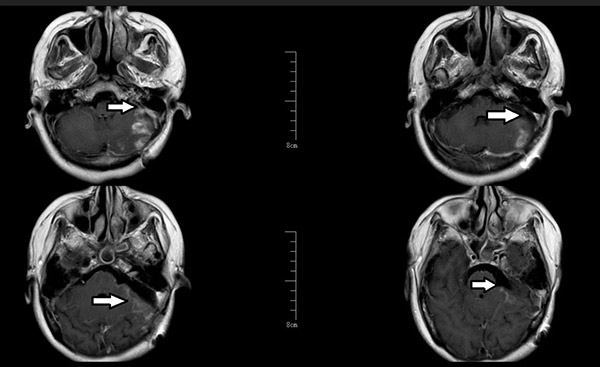

复查显示:

✓肿瘤100%清除✓听力完全保留 ✓ 面部肌肉活动正常

术后增强磁共振